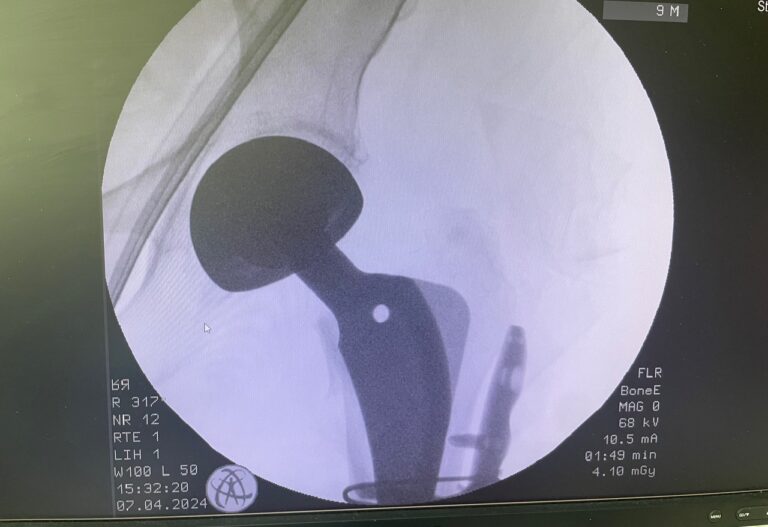

- Κάταγμα μηριαίου αυχένα (πολύ συχνό στους ηλικιωμένους)

- Διαφυσιακά κατάγματα μηριαίου ή κνήμης

Διάγνωση

- Ακτινογραφία

- Χειρουργική αποκατάσταση (πλάκες, βίδες, ενδομυελικοί ήλοι)